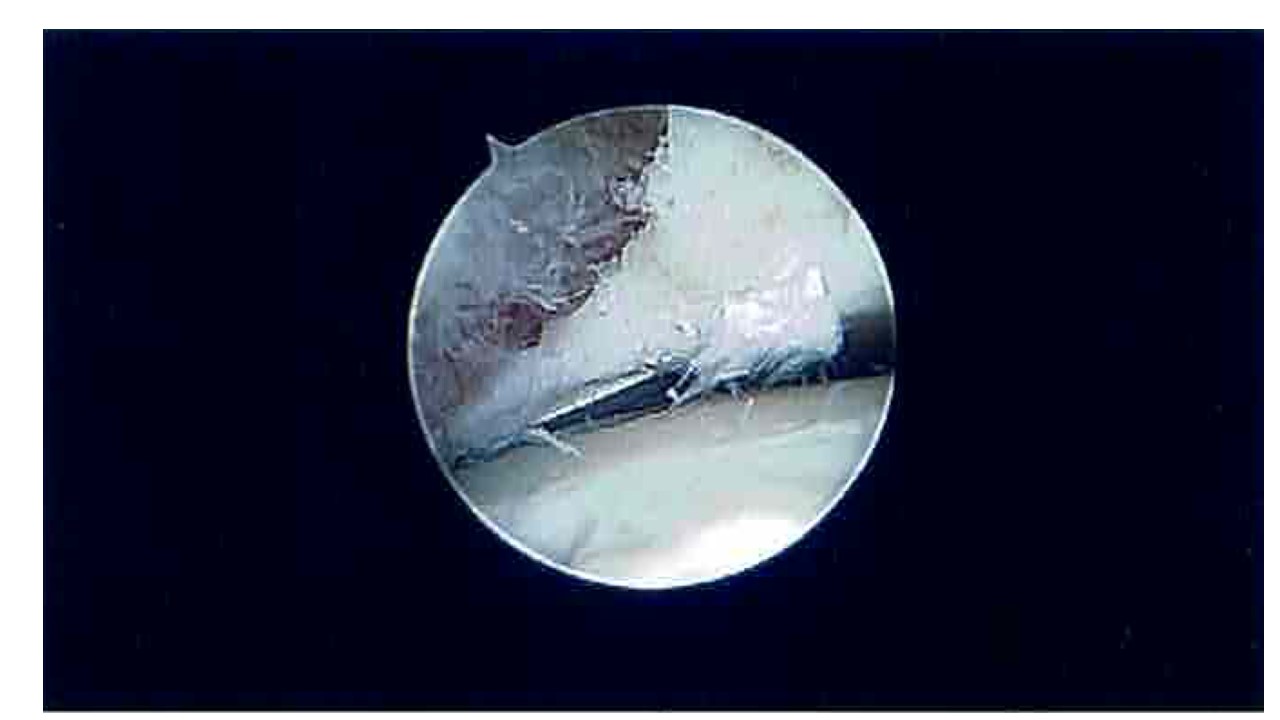

Most anterior ankle joint bone spurs can be removed using “key-hole” (arthroscopic) surgery which is usually carried out as a day case. This type of surgery is very common and offers very good results provided the rest of the ankle joint is in good condition.

Before and after pictures of an anterior ankle bone-spur removed with an arthroscopic burr.